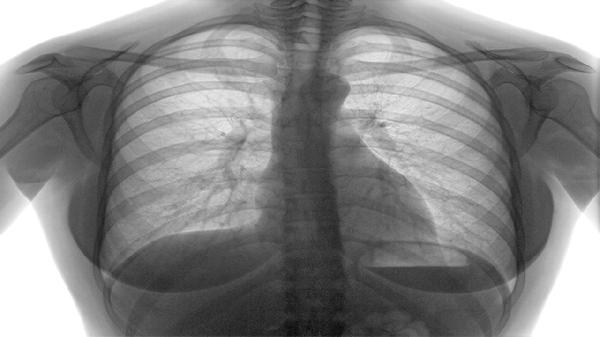

知母皂苷能够降低肺组织内白介素-6水平,减少气道高反应性。适用于肺炎恢复期遗留的刺激性咳嗽,胸部X线显示炎症吸收但咳嗽未愈时,可配合阿奇霉素分散片完成抗感染后治疗。